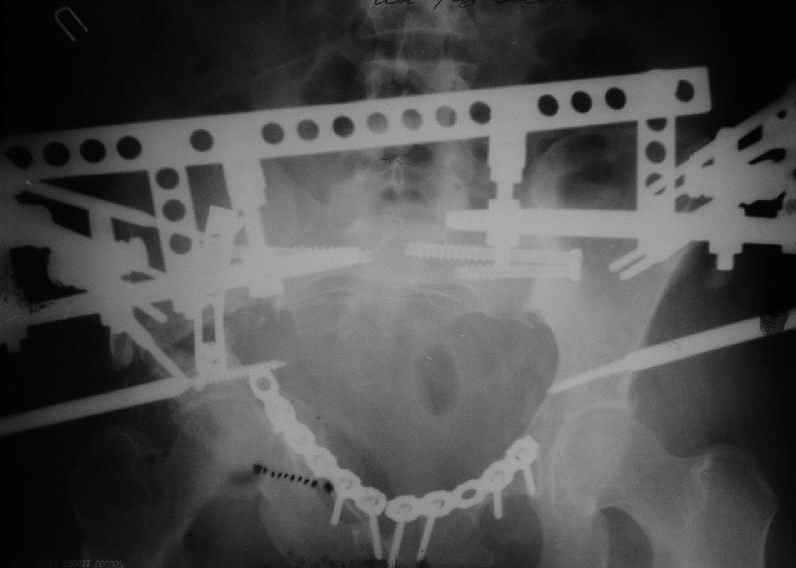

Уважаемые коллеги, вашему вниманию предлагается продолжеие истории лечения больной с двусторонней деформацией таза . Итак, 26.01.05 была выполнена остеотомия правой подвздошной кости, низведение правой вертлужной области, остеосинтез правой подвздошной кости пластиной, чрескостный остеосинтез аппаратом таз-бедро.  Снимок после первого этапа | После заживления раны и стабилизации общего состояния 22.02.05 была выполнена реконструкция переднего отдела таза, синтез лонных костей пластиной, опора с бедра демонтирована, выполнено введение илиосакральных винтов с обеих сторон. В настоящее время рана зажила первичным натяжением, больная ходит с двумя костылями без опоры на правую нижнюю конечность. С интересом ждем ваши комментарии.